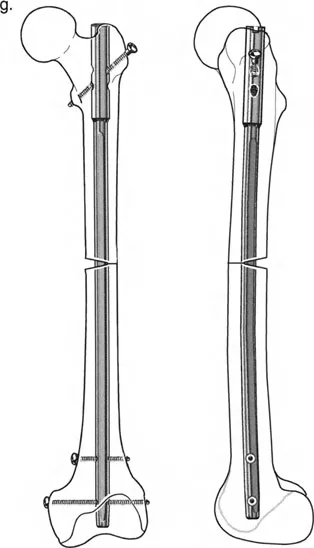

تثبيت المسمار الداخلي بمساعدة المثبت الخارجي (FAN) هو تقنية جراحية حديثة تجمع بين دقة المثبت الخارجي المؤقت واستقرار المسمار الداخلي الدائم، مما يوفر تصحيحًا فائقًا لتشوهات العظام المعقدة مع راحة فورية للمريض وتعافٍ أسرع.

الخلاصة الطبية السريعة: تثبيت المسمار الداخلي بمساعدة المثبت الخارجي (FAN) هو تقنية جراحية حديثة تجمع بين دقة المثبت الخارجي المؤقت واستقرار المسمار الداخلي الدائم، مما يوفر تصحيحًا فائقًا لتشوهات العظام المعقدة مع راحة فورية للمريض وتعافٍ أسرع.